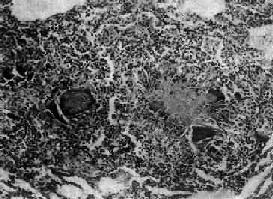

图18-1 结核性肉芽肿 结节中央为干酪样坏死,周围绕有类上皮细胞、Langhans巨细胞以及淋巴细胞等 3.坏死为主的变化 在结核杆菌数量多、毒力强,机体抵抗力低或变态反应强烈的情况下,上述渗出性和增生性病变均可继发干酪样坏死。病变一开始便呈现干酪样坏死者十分少见。由于坏死组织含脂质较多(脂质来自破坏的结核杆菌和脂肪变性的单核细胞)而呈淡黄色,均匀细腻,质地较实,状似奶酪,故称干酪样坏死。镜下见为红染无结构的颗粒状物。干酪样坏死的形态特点,特别是肉眼所见对结核病的病理诊断具有一定的意义。干酪样坏死物中大都含有一定量的结核杆菌。 干酪样坏死灶内含有多量抑制酶活性的物质,故坏死物可不发生自溶、排出,也不易被吸收。但有时也能发生软化和液化,形成半流体物质。随着液化,结核杆菌大量繁殖,更进一步促进液化的发生。液化固有利于干酪样坏死物的排出,但更重要的是可成为结核菌在体内蔓延扩散的来源,是结核病恶化进展的原因。 以上渗出、增生和坏死三种变化往往同时存在而以某一种改变为主,而且可互相转化。例如渗出性病变可因适当治疗或机体免疫力增强而转化为增生性病变;反之,在机体免疫力下降或处于较强的变态反应状态时,原来的增生性病变则可转变为渗出性、坏死性病变,或原来的渗出性病变转化为坏死性病变。因此,在同一器官或不同器官中的结核病变是复杂多变的。 【结核病基本病变的转化规律】 结核病变的发展和结局取决于机体抵抗力和结核菌致病力之间的矛盾关系。当人体抵抗力增强时,细菌逐渐被控制而消灭,结核病变转向愈复;反之,则转向恶化。 1.转向愈复 主要表现为病变的吸收消散、纤维化、纤维包裹和钙化。 (1)吸收消散:为渗出性病变的主要愈复方式。渗出物逐渐通过淋巴道吸收,病灶缩小或完全吸收消散。较小的干酪样坏死灶和增生性病变如治疗得当也可被吸收。 (2)纤维化、纤维包裹及钙化:增生性结核结节转向愈复时,其中的类上皮细胞逐渐萎缩,结节周围的增生纤维母细胞长入结核结节形成纤维组织,使结节纤维化。未被完全吸收的渗出性病变也可通过机化而发生纤维化。小的干酪样坏死灶(1~2mm)可完全纤维化;较大者难以完全纤维化而由坏死灶周围的纤维组织增生,将干酪样坏死物质加以包裹,以后干酪样坏死逐渐干燥浓缩,并有钙质沉着而发生钙化。 病灶发生纤维化后,一般已无结核杆菌存活,可谓完全痊愈。在被包裹、钙化的干酪样坏死灶中仍有少量细菌存活,病变只处于相对静止状态(临床痊愈),当机体抵抗力下降时病变可复燃进展。 2.转向恶化 主要表现为病灶扩大和溶解播散。 (1)病灶扩大:病变恶化进展时,在病灶周围出现渗出性病变(病灶周围炎),其范围不断扩大,并继而发生干酪样坏死。坏死区又随渗出性病变的扩延而增大。 (2)溶解播散:干酪样坏死物发生溶解液化后,可经体内的自然管道(如支气管、输尿管等)排出,致局部形成空洞。空洞内液化的干酪样坏死物中含有大量结核杆菌,可通过自然管道播散到其他部位,引起新的病灶。如肺结核性空洞通过支气管播散可在同侧或对侧肺内形成多数新的以渗出、坏死为主的结核病灶。此外,结核杆菌还可通过淋巴道蔓延到淋巴结,经血道播散至全身,在各器官内形成多数结核病灶。

第一节 结核病结核病(tuberculosis)是由结核杆菌引起的一种慢性传染病。全身各器官均可发生,但以肺结核最为多见。其病变特征是结核结节形成并伴有不同程度的干酪样坏死。 【病因和发病机制】 结核病的病原菌是结核杆菌,对人致病的主要类型为人型和牛型。结核杆菌含有脂质、蛋白和多糖类三种成分:①脂质:特别是脂质中的糖脂更为重要。糖脂的衍生物之一称索状因子(cord factor),能使结核杆菌在培养基上生长时呈蜿蜒索状排列。这种形式生长的结核杆菌在动物体内具有毒力。另一种糖脂为蜡质D(wax D),将其与结核菌体蛋白一起注入动物体内,能引起强烈的变态反应,造成机体的损伤。此外,磷脂还能使炎症灶中的巨噬细胞转变为类上皮细胞,从而形成结核结节。脂质除可能与毒力有关外,还可保护菌体不易被巨噬细胞消化。②蛋白:具有抗原性,与蜡质D结合后能使机体发生变态反应,引起组织坏死和全身中毒症状,并在形成结核结节中发挥一定的作用。③多糖类:可引起局部中性粒细胞浸润,并可作为半抗原参与免疫反应。 结核病主要经呼吸道传染。肺结核(主要是空洞型肺结核)病人在谈话、咳嗽和喷嚏时,从呼吸道排出大量带菌微滴(每个微滴可含10~20个细菌)。吸进这些带菌的微滴即可造成感染。少数病人可因食入带菌的食物经消化道感染。细菌经皮肤伤口感染者极少见。 结核病的发生和发展取决于很多因素,其中最重要的是感染的菌量及其毒力的大小和机体的反应性(免疫反应或变态反应)。后者在结核病的发病学上起着特别重要的作用。 目前一般认为,结核病的免疫反应以细胞免疫为主,即T细胞起主要作用。它在受到结核菌的抗原刺激后可转化为致敏的淋巴细胞。当再次与结核杆菌相遇时,致敏的淋巴细胞可很快分裂、增殖,并释放出各种淋巴因子,如巨噬细胞趋化因子、集聚因子、移动抑制因子和激活因子等。这些因子可使巨噬细胞移向结核杆菌,并聚集于该处不再移动,这样就能把结核杆菌限制在局部不致扩散。同时还激活了巨噬细胞,使巨噬细胞体积增大,伪足形成活跃,溶酶体含量增加,细胞内pH下降等。这些改变有助于使吞入的细菌更易被水解、消化和杀灭。此外,激活后的T细胞还可释放其他淋巴因子,加强这一免疫反应,如结核杆菌的生长抑制因子能通过巨噬细胞特异性地抑制细胞内结核杆菌的繁殖而获得免疫。结核结节的形成就是上述各种反应的具体形态学表现。 结核病时发生的变态反应属于IV型(迟发性)变态反应。结核菌素试验就是这种反应的表现,本质上亦为细胞免疫反应。 结核病免疫反应和变态反应常同时发生并相伴出现,但两者关系如何及其对结核病的发生、发展有何影响等问题,长期来尚未解决。在结核病的诊断方面,基因诊断作为结核菌的非培养诊断技术是近年来结核病快速诊断的一项重大突破。它乃借分析结核菌的遗传物质核酸而特异,敏感、快速地检测和鉴定结核杆菌。目前用于结核菌检测和鉴定的基因诊断方法有基因探针技术、染色体指纹技术和PCR技术。 【结核病的基本病变】 结核杆菌在机体内引起的病变属于特殊性炎症,虽其病变具有一般炎症的渗出、坏死和增生三种基本变化,但有其特异性。由于机体的反应性(免疫反应和变态反应)、菌量及毒力和组织特性的不同,可出现以下不同的病变类型: 1.渗出为主的病变 出现在结核性炎症的早期或机体免疫力低下,菌量多、毒力强,或变态反应较强时,表现为浆液性或浆液纤维素性炎。早期病灶内有中性粒细胞浸润,但很快被巨噬细胞取代。在渗出液和巨噬细胞内易查见结核杆菌。此型变化好发于肺、浆膜、滑膜和脑膜等处,说明与组织结构特性亦有一定的关系。渗出性变化可完全吸收不留痕迹,或转变为以增生为主或以坏死为主的病变。 2.增生为主的变化 当菌量较少,毒力较低或人体免疫反应较强时,则发生以增生为主的变化,形成具有一定诊断特征的结核结节(结核性肉芽肿)。单个结核结节肉眼不易看见,三、四个结节融合成较大结节时才能见到。其境界分明,约粟粒大小,呈灰白半透明状,有干酪样坏死时则略呈黄色,可微隆起于器官表面。 结核结节(tubercle)是在细胞免疫基础上形成的,由类上皮细胞(epithelioid cell)、Langhans巨细胞加上外围局部集聚的淋巴细胞和少量反应性增生的纤维母细胞构成。当有较强的变态反应发生时,结核结节中便出现干酪样坏死。巨噬细胞体积增大逐渐转变为类上皮细胞,呈梭形或多角形,胞浆丰富,染淡伊红色,境界不清。核呈圆或卵圆形,染色质甚少,甚至可呈空泡状,核内可有1~2个核仁。多数类上皮细胞互相融合乃形成Langhans巨细胞,为一种多核巨细胞,体积很大,直径可达300μm,胞浆丰富,核与类上皮细胞核的形态大致相同,核数由十几个到几十个不等,有超过百个者。核排列在胞浆的周围呈花环状、马蹄形或密集在胞体的一端(图18-1)。